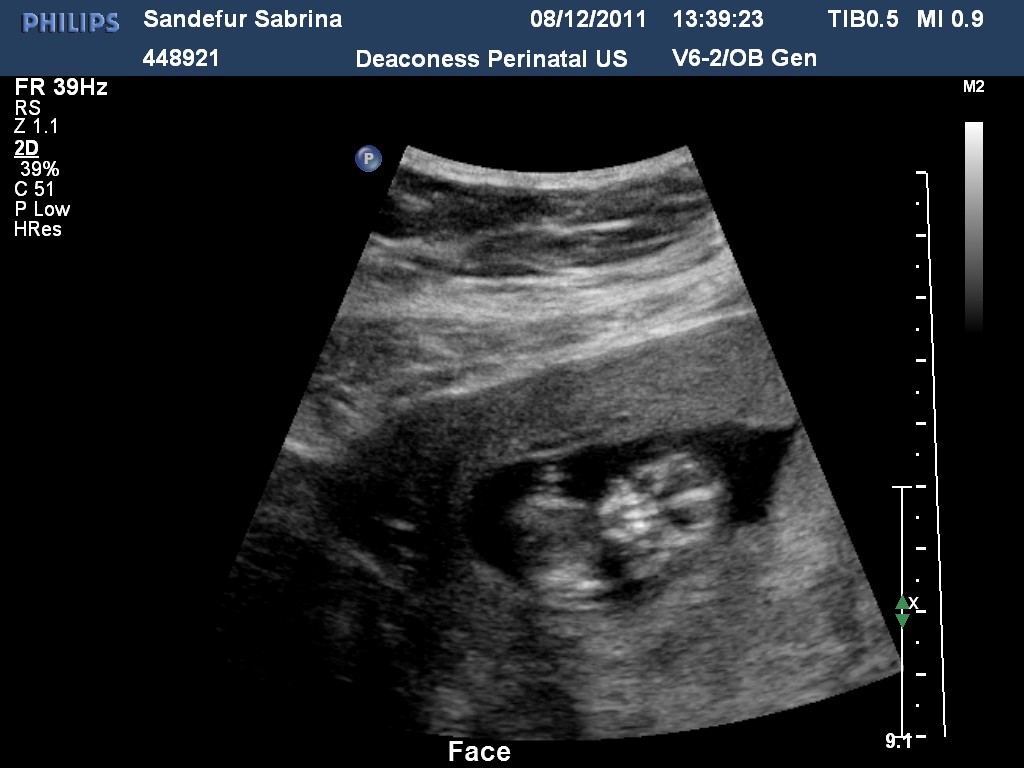

12 weeks!!!  I am slowly getting there!  Almost to my 2nd trimester!!  I had my NT/first trimester screening done on 8/12.  The u/s came back perfect, and the b/w came back negative yesterday.  =)  I am still waiting on the results of all the other lab they drew.  They did my chromosones, and the m/c panel stuff, etc.  I imagine they will call me back with the results in the next week or so.  I am not really too worried about it.  =)  As of today, my total weight loss is at 15 pounds.  5 more to go.  LOL!  There has to be some benefit of being ill!!  =P  I am still using my doppler, of course.  Hb is always ranging in the 160's.

Ultrasound...

I had my ultrasound this afternoon.  It was great seeing Skittle again!  She was bouncing all over the place!  She was measuring about 3-4 days ahead of schedule, so that made me feel good.  We did find the source of the bleeding.  I have a sub chorionic hemorrhage(SCH).  The SCH is not very big, thank goodness, and hopefully will start clearing up so that I won't have anymore spotting.  Being a professional TP checker is NOT fun!  Makes you fearful every time you have to go to the bathroom, scared what you might find!  I am just thankful that Skittle seemed to be doing just dandy in her momma's tummy!  ♥  I can't ask for anything else right now!